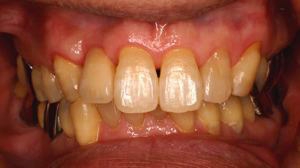

インセラム(オールセラミック)症例①

治療前治療前インセラム(オールセラミック)冠による修復。 主訴は前歯が汚い 金属を使わないオールセラミックでの治療を勧めた。 術前 治療後治療後術後